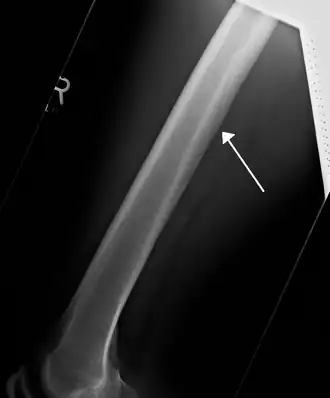

![]() A nutrient canal feeding the femur seen on X-ray | |

All bones possess larger or smaller foramina (openings) for the entrance of blood-vessels; these are known as the nutrient foramina, and are particularly large in the shafts of the larger long bones, where they lead into a nutrient canal, which extends into the medullary cavity. The nutrient canal (foramen) is directed away from the growing end of bone. The growing ends of bones in upper limb are upper end of humerus and lower ends of radius and ulna. In lower limb, the lower end of femur and upper end of tibia are the growing ends.[1] The nutrient arteries along with nutrient veins pass through this canal. A nutrient canal is found in long bones, in the mandible, and in dental alveoli.[2] In long bones the nutrient canal is found in the shaft.